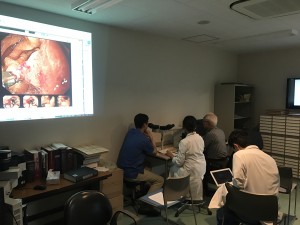

柳澤先生病理カンファレンス

2016.12.16[ 勉強会 ]

柳澤先生病理カンファレンス

当院では月1回、元京都府立医科大学臨床病理学教室教授・現京都第一赤十字病院病理診断科特別顧問の柳澤昭夫先生をお招きして病理カンファを行っています。

柳澤先生は消化管部長:江頭先生の病理の師匠であり,そのご縁があって当院へ来て頂き,毎回白熱した議論が繰り広げられております。

今回も病理・臨床側合わせて15症例前後の白熱したdiscussionが行なわれました。

全部はご紹介できないので私が提示した一例をご紹介します。

前庭部大弯の20mm弱の白色調0-Ⅱa病変でESDを施行した症例です。

術前診断としては病変は柔らかく,酢酸撒布をしても表面構造がしっかりと確認でき,分化型早期胃癌(深達度M)の診断でESD導入となりました。

しかし,病理結果としては先進部にmucを有しly1のSM1の診断となりました。

この症例でどうして術前診断を誤ったか,病理上なぜこのような形態を呈するかと白熱した議論が繰り広げられました。

やはりmucがSM浸潤した場合は病変は柔らかいためあまり粘膜下腫瘍様の形態は呈さず,伸展刺激でも容易に変形するため注意が必要であると感じました。

当院では忙しいながらもこの様に一例一例の積み重ねを大切にして日々の診療を行っています。